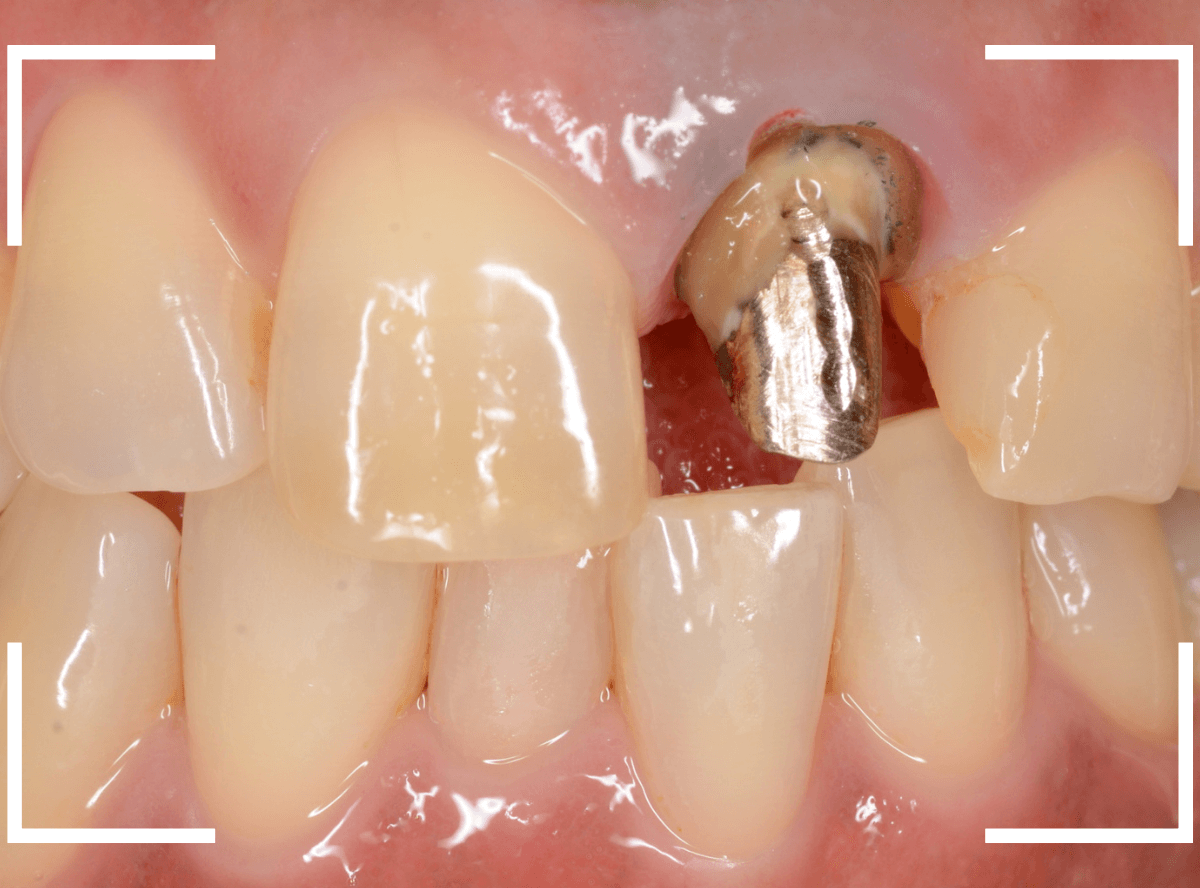

さし歯の中には大きなメタル・コアが入っています。。。

さし歯の周りの歯肉が若干黒ずんでるのも、これが原因でしょう。

せっかくさし歯をやり直すのであれば、このメタル・コアもやりなおしたいところです。

かなり怖かったですが、患者さんにも頑張っていただいて、さし歯を除去後、時間をかけて慎重にメタルコアを除去しました。

無事にメタルコアを除去できましたので、ファイバーコアに置き換えます。